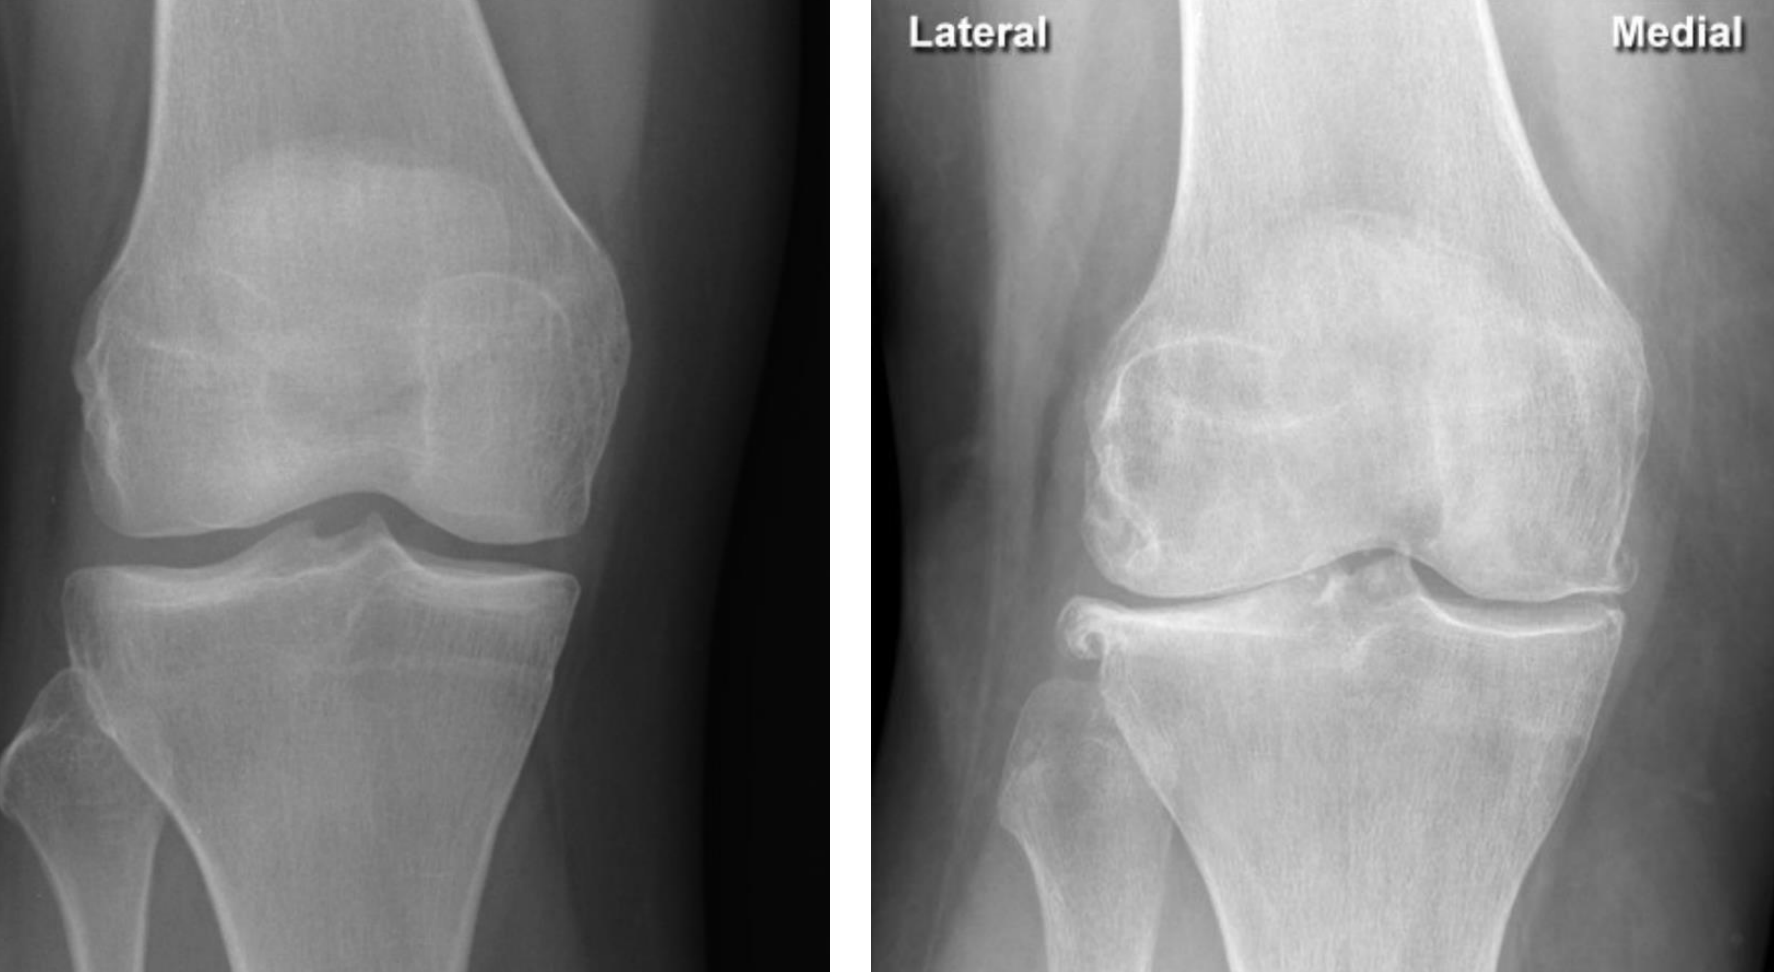

loss of alignment of the 3rd metatarsophalangeal joint

describe the scan + indication

Loss of joint space (fusion of bones) indicating cartilage loss at the 1st metatarsophalangeal joint with osteophytes (sign of OA)

Loss of joint space (fusion of bones) indicating cartilage loss at the lip of the femur with osteophytes

(indicating OA, sometimes also formation of cysts - erosions are not a feature)